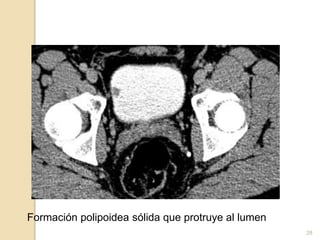

Hallazgos

La vejiga se encuentra parcialmente distendida. Sus paredes

se encuentran levemente engrosadas en forma difusa, y en

su aspecto lateral derecho se identifica una formación

polipoidea sólida que protruye al lumen de 10×11 mm.

En el decúbito prono, el aspecto antero-inferior izquierdo de

la vejiga se insinua a hernia inguinal ipsilateral de 14 mm de

diámetro.

Impresión

Lesión polipoidea endoluminal vesical derecha. Correlacionar

con cistocopía. Leve engrosamiento parietal difuso vesical.

Hernia inguinal izquierda , con insinuación de la pared

antero-inferior-izquierda de la vejiga en posición decubito

prono.

Formación polipoidea sólida que protruye al lumen